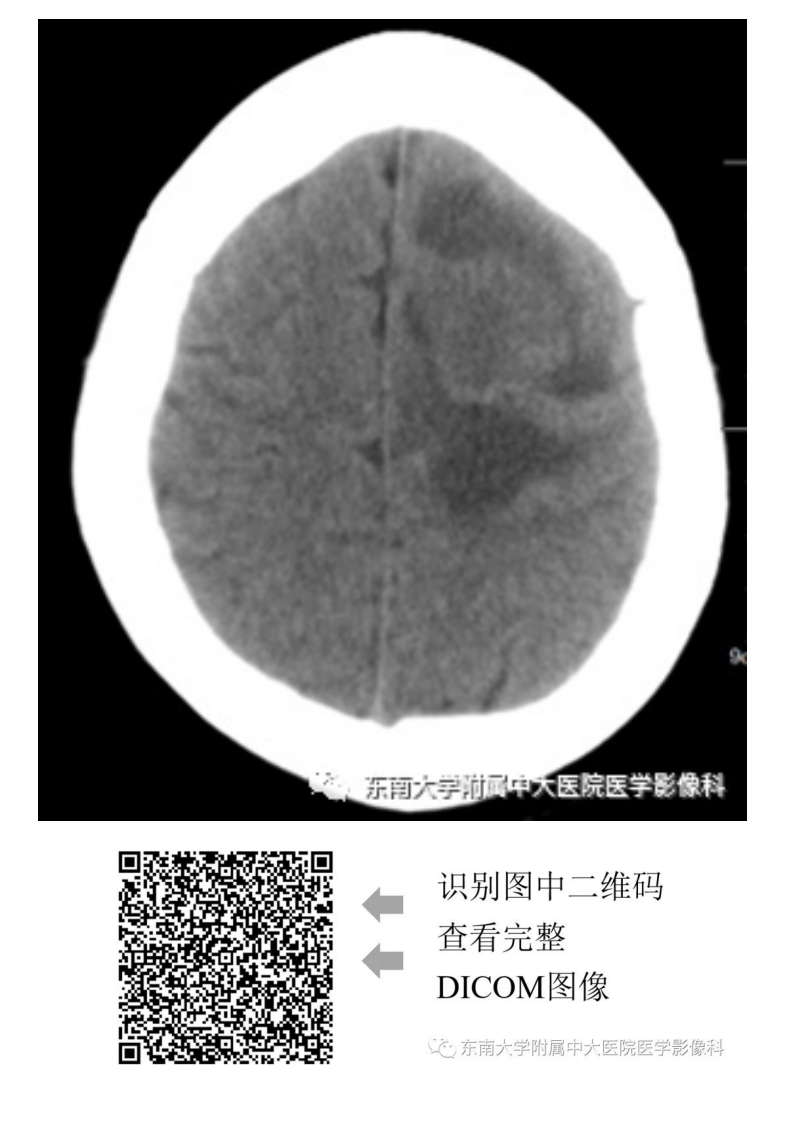

20190909_2【晨读结果公布】2019.09.09神经系统疾病.pdf